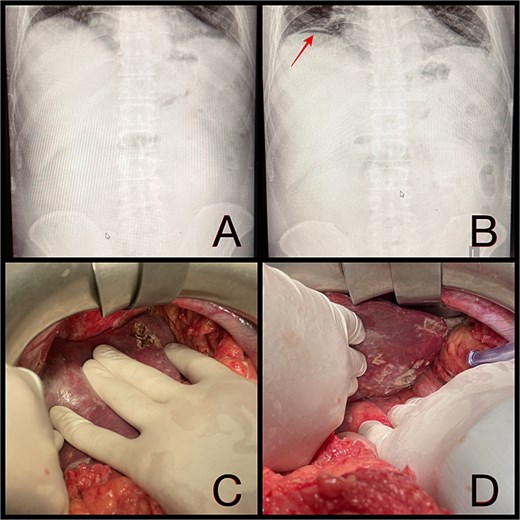

Within 2 hr of admission, the patient’s condition deteriorated rapidly, developing septic shock and peritoneal signs. Repeat abdominal X-ray revealed free subdiaphragmatic air. Given the acute deterioration and new findings, urgent laparotomy was indicated for suspected gastric perforation.

Intraoperatively, a ruptured liver abscess in segment II was found, perforating both the diaphragmatic and visceral hepatic surfaces. There was purulent discharge into the peritoneal cavity, predominantly in the upper abdomen. No gastrointestinal perforation was identified. Abdominal lavage, liver biopsy, and drainage were performed, followed by laparostomy (Fig. 1).

(A and B) Abdominal radiographs showing progression from no free gas (A) to a crescent of pneumoperitoneum beneath the right hemidiaphragm (B, arrow) within 2 hr. (C and D) Intraoperative findings of a ruptured pyogenic liver abscess in segment II, perforating both the diaphragmatic and visceral hepatic surfaces.